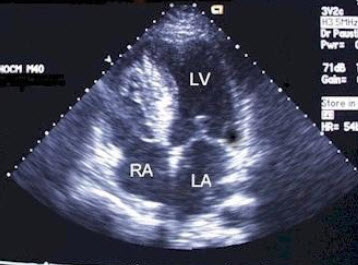

该食管超声心动图显示图像为()

A.房间隔缺损(上腔型)

B.房间隔缺损(下腔型)

C.房间隔缺损(中央型)

D.房间隔缺损(混合型)

E.冠状静脉窦扩张